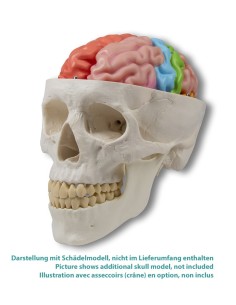

Dal cranio in 22 parti con incastri magnetici ai modelli di colonna vertebrale, da quelli di articolazioni a quelli di cuore, ogni pezzo della nostra collezione è progettato per un’immersione totale nello studio dell’anatomia umana. I nostri modelli, realizzati tramite scansioni di ossa vere, garantiscono un’esperienza tattile autentica e una fedeltà di peso quasi identica agli originali.